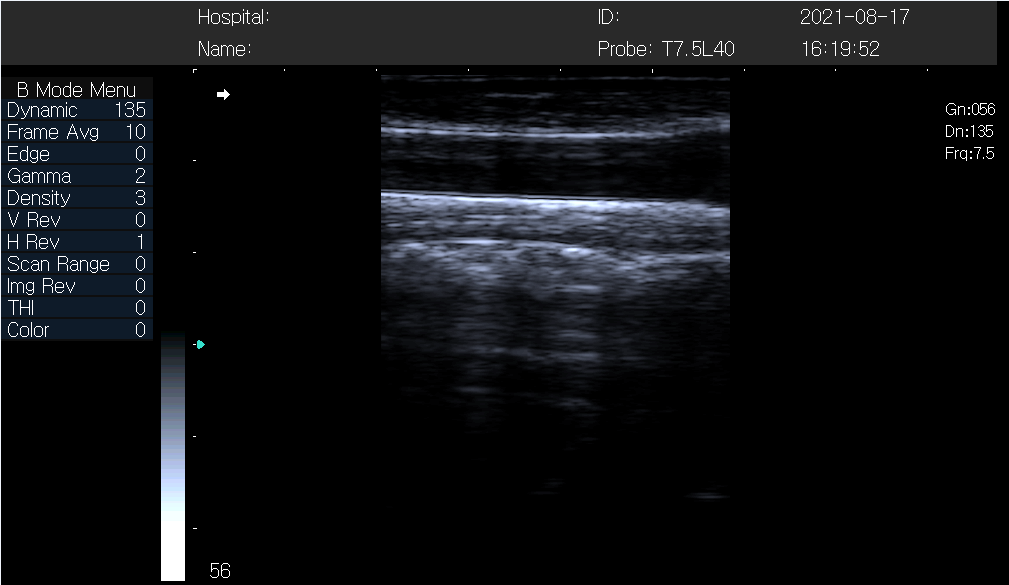

Ultrasonic examination is to observe the reflection of ultrasonic wave by the human body, is to illuminate the body with weak ultrasonic wave, the reflected wave of tissue is processed graphically, and the image can indirectly reflect the structure of each layer of tissue in a part of the human body. Abdominal ultrasonography is suitable for the diagnosis of pain in liver, gallbladder, bile duct, spleen, pancreas, kidney, adrenal gland, bladder, prostate and other organs. Ultrasonic examination method is simple, high diagnostic accuracy, no harm to the patient. Ultrasound decays quickly in air and is not suitable for examination of hollow organs.

This examination can quickly check the size and shape changes of liver, gallbladder, bile duct, spleen, pancreas, kidney, adrenal gland, bladder, prostate and other organs; Whether in a normal position; Whether there is space occupying in the viscera; Placeholders are substantial or liquid, such as cysts, hematoma and abscesses, etc., and to a certain extent, it can identify whether the placeholders are benign or malignant, whether they are oppressed by surrounding masses or organs; Still can fish abdominal cavity, pelvic swollen lymph node; The contraction of gallbladder can be observed to judge the function of gallbladder; Can also accurately judge whether there is ascites, even if a small amount of ascites can also be measured.